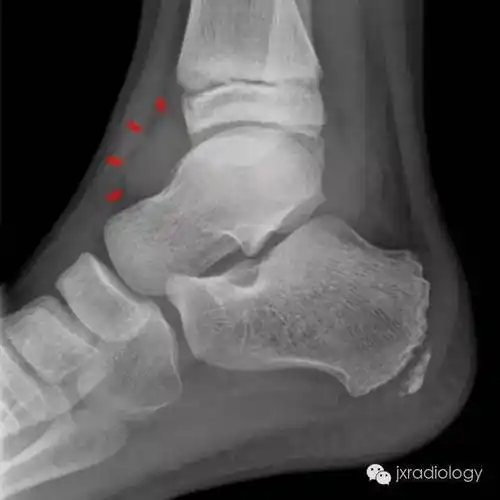

infectious arthritis感染性关节炎synovitis滑膜炎rheumatoid